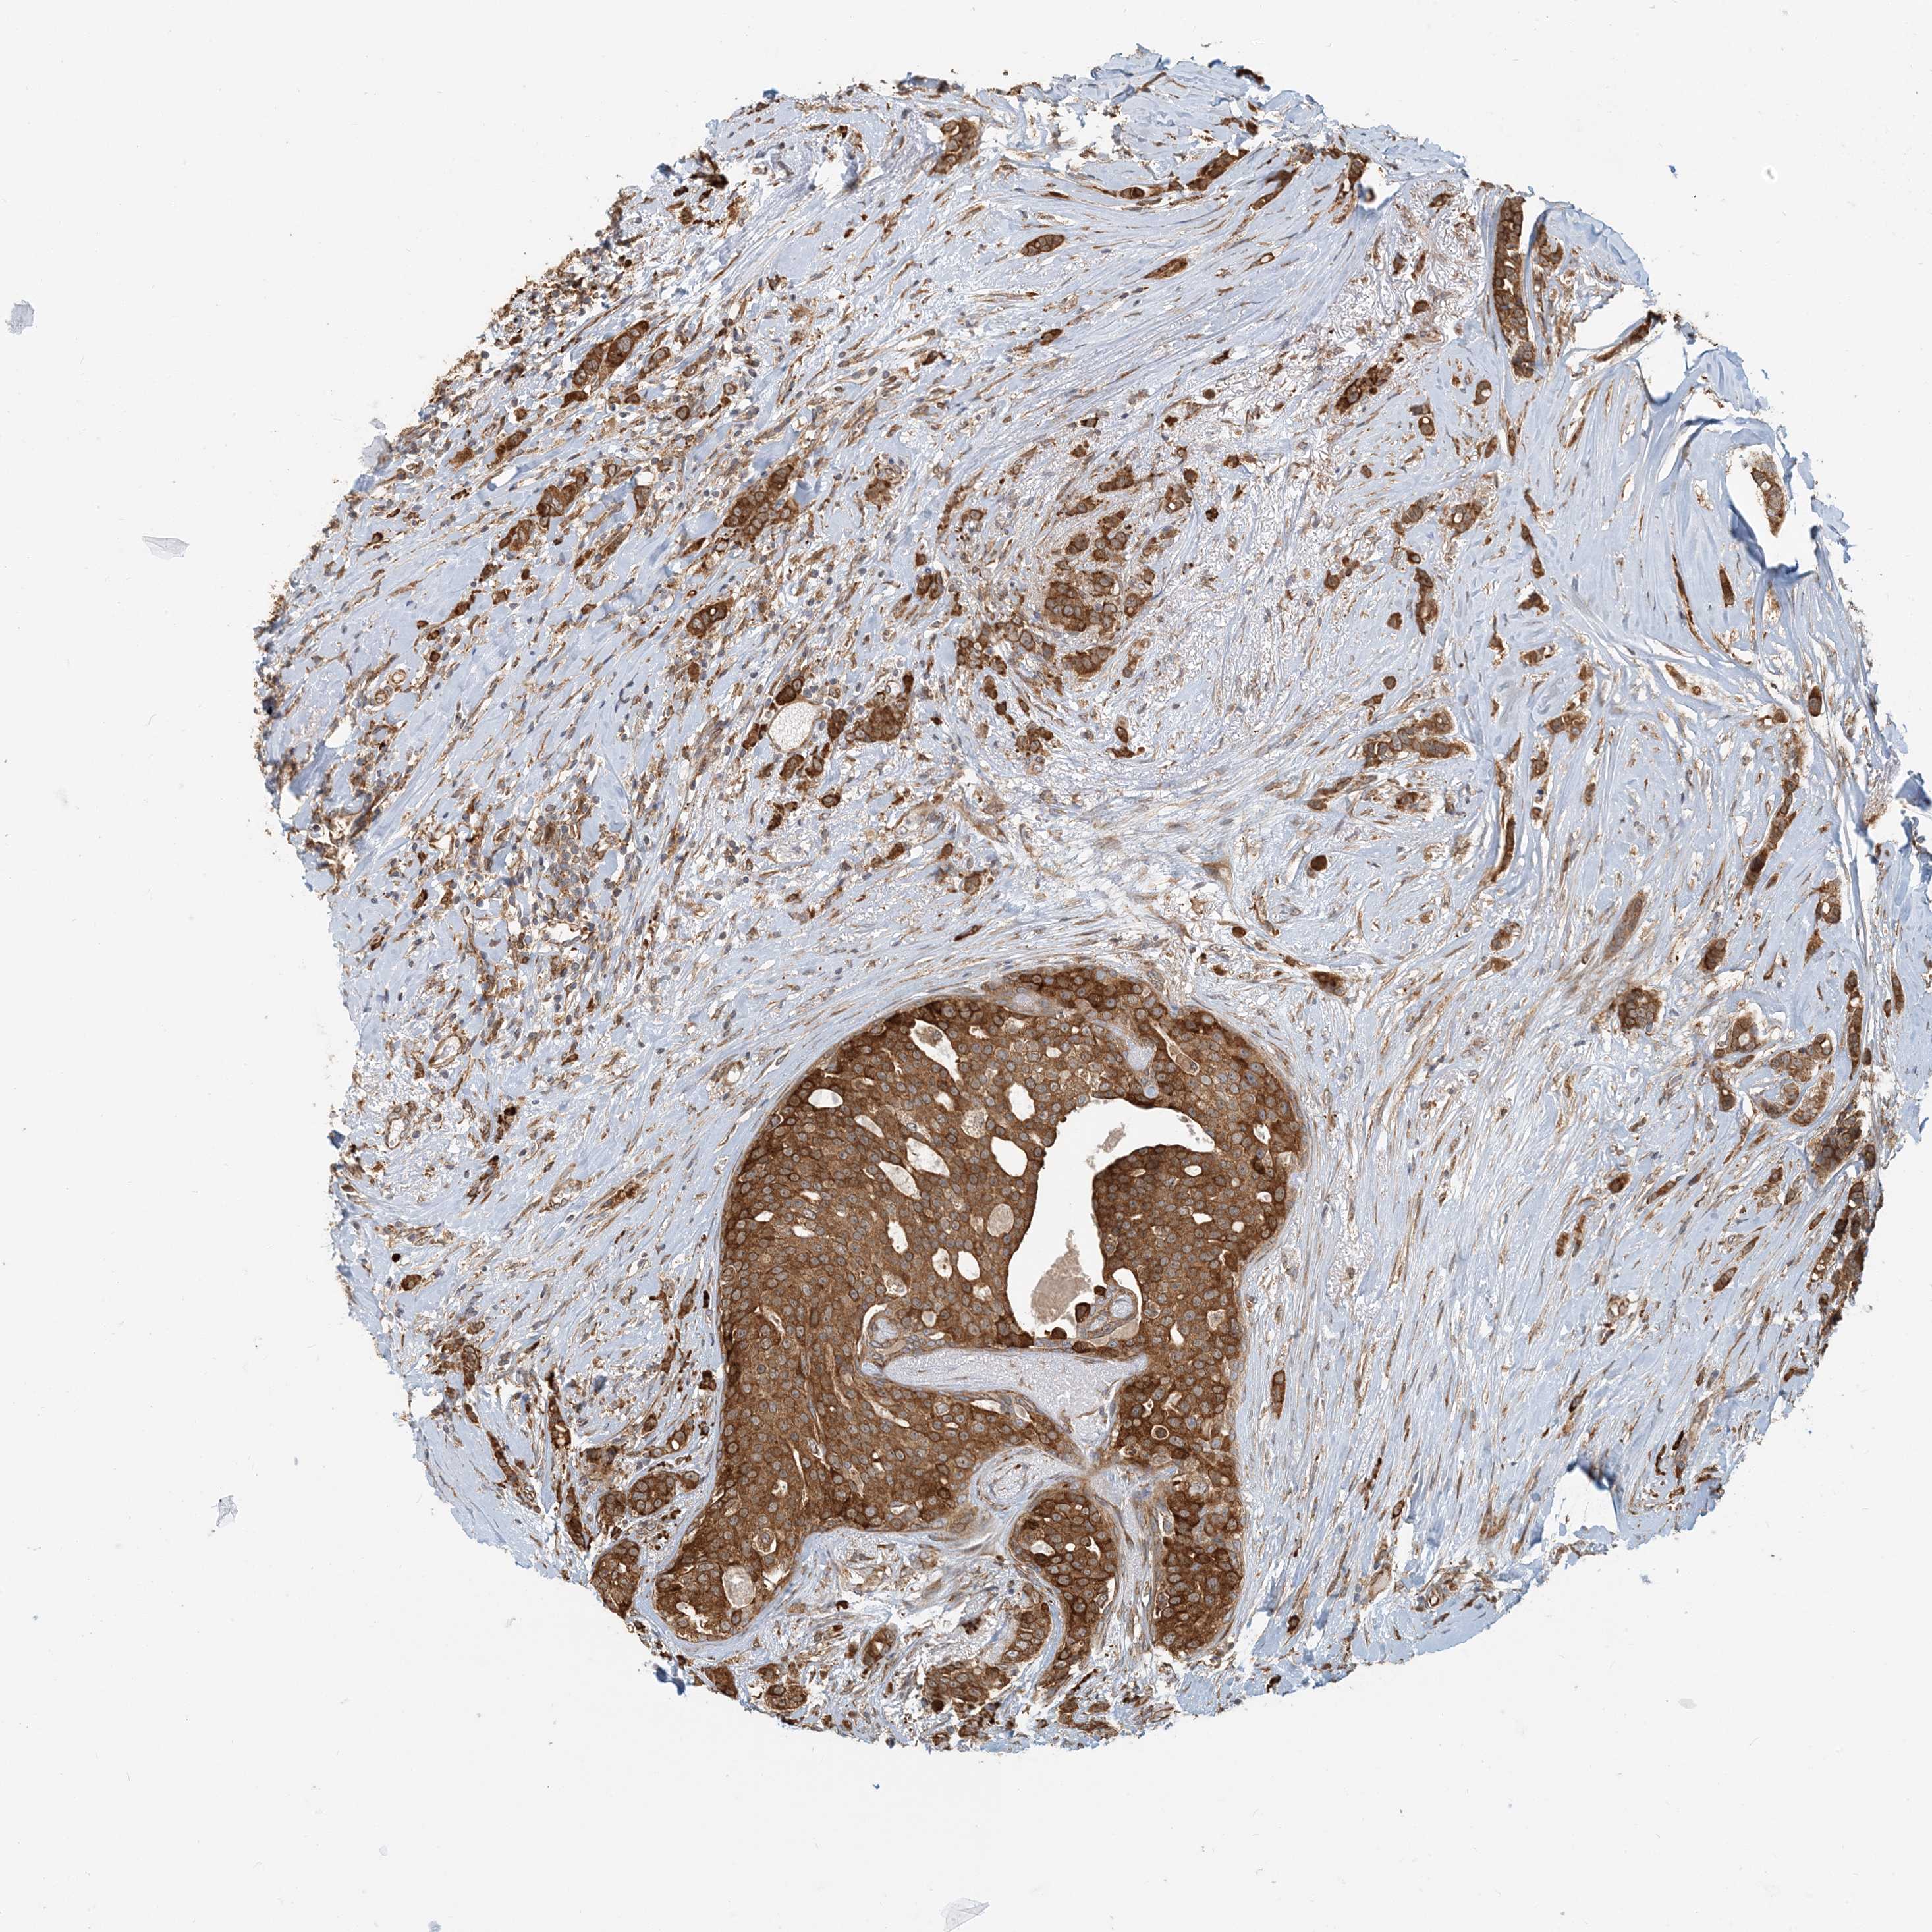

CANCER BREAST CANCER Show tissue menu

BRCA TCGA BRCA VALIDATION PROTEIN EXPRESSION

ANTIBODIES